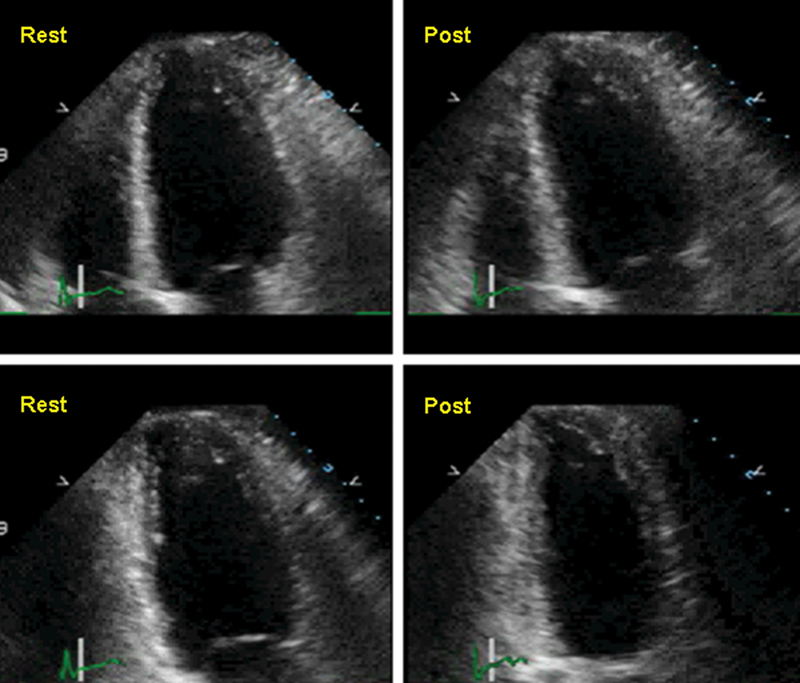

فحوصات تشخيصية لبعض امراض القلب والشرايين التاجية